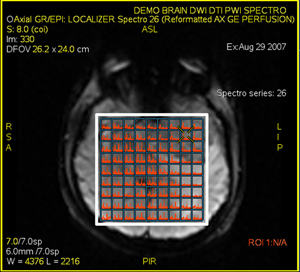

Figure 1. Spectroscopy tab > Voxel Correction tab

• Only Selected Voxels or All voxels can be selected.

• Selected Voxels, only corrects the active voxels, colored in green (individual voxels or ROI).

• All voxels, corrects for all voxels in the CSI VOI.

• Select Reset to reset the values of the specific function: Phase Correction, Frequency Shifting or Baseline Correction.

• Select Reset All to reset all the value(s) on the tab to the default factory values.

• Select Apply to re-calculate the metabolites based on the changes you made for the Baseline Correction.

• Select Save All to save changed selections as the new default values.